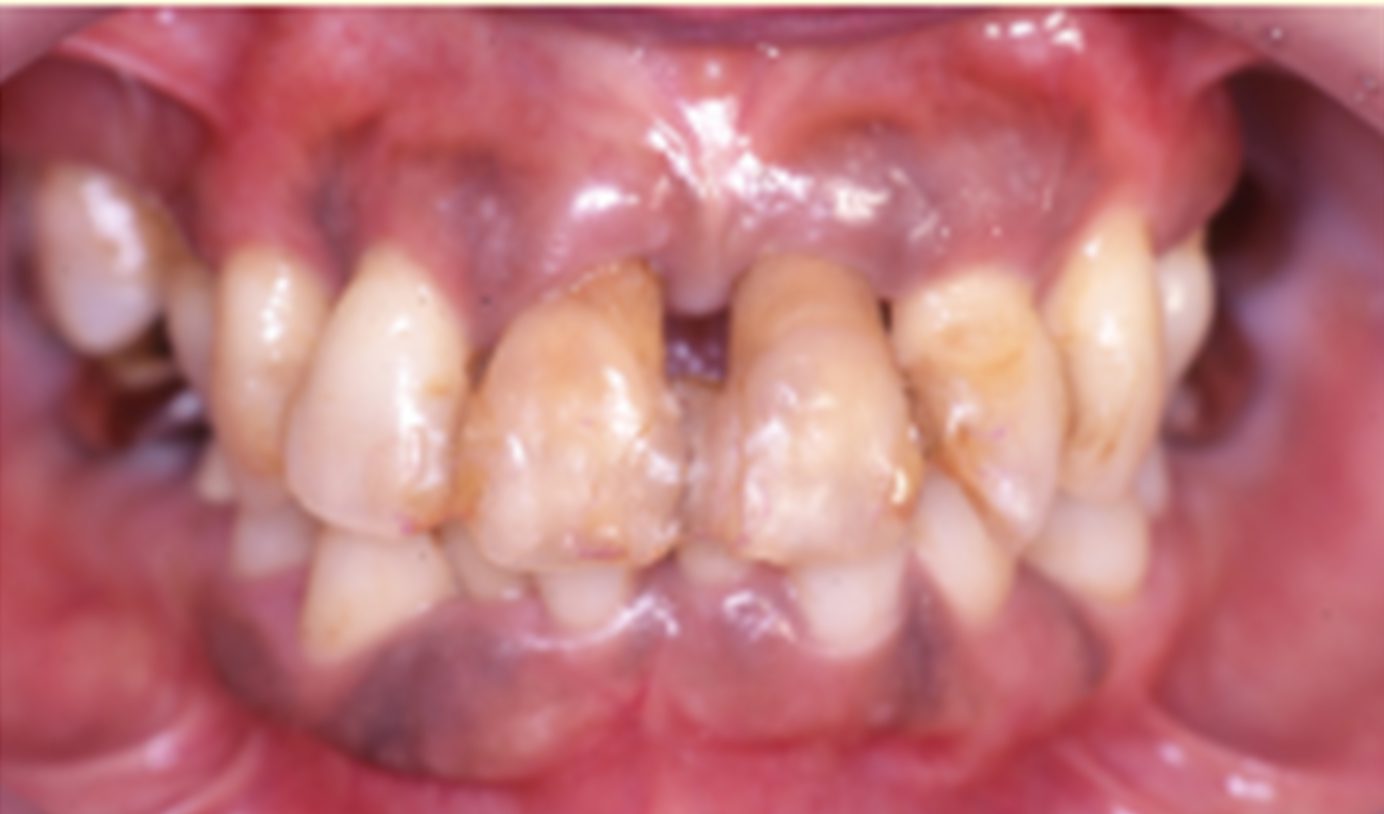

喫煙によって歯周病にかかってしまった50代女性(写真:日本歯周病学会提供)

喫煙していると歯周病菌が増えやすくなることがわかっています。

歯を失うだけでなく、全身の健康にも影響するのが歯周病の怖いところ。